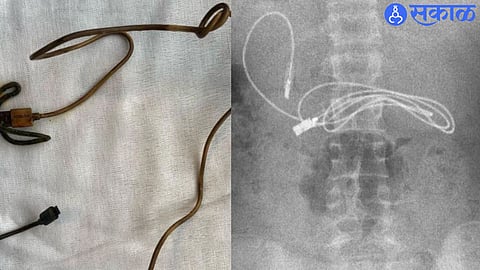

एका मुलाला तीव्र पोटदुखी आणि उलट्या होत असल्याने त्याला डॉक्टरकडे नेण्यात आलं. डॉक्टरांनी त्याचा एक्स-रे रिपोर्ट काढला आणि हा रिपोर्ट पाहून सर्वांच्याच अंगावर काटा आला. कारण एक्स-रे रिपोर्टमध्ये या मुलाच्या पोटात 3 फूट लांब मोबाईल चार्जर केबल आणि केसांची क्लिप दिसून आली.

त्वरीत या मुलावर शस्त्रक्रिया करावी लागली आणि चार्जर केबल आणि हेअर क्लिप काढण्यात आली. या संबंधीत फोटो सध्या इंस्टाग्रामवर व्हायरल होत आहे.